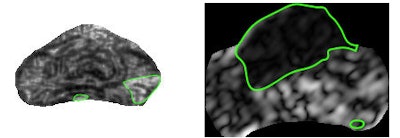

| Sample textural representations found to be highly discriminatory for peripheral zone tumor (left) and central gland tumor (right) show difference in texture with cancer region (green outline) and rest of prostate. |

| Classification heat maps (above) show areas in red that correspond to a high probability of cancer. Green outlines on the previous textural representations correspond well with red regions on the heat maps. The authors found that different classifiers and features performed best for each central gland or peripheral zone cancer. |

With an area under the curve (AUC) of 0.87, the QDA classifier performed the best for detecting central gland prostate cancer. The boosted decision-tree classifier, however, performed the best (AUC = 0.75) for detecting peripheral zone cancer.

Notably, the frequently used SVM classifier turned in poor AUC in both central gland (0.71) and peripheral zone (0.55) prostate cancers, Viswanath said.

"A simple [QDA] classifier, known to be less dependent on the size and quality of the imaging data cohort, appears to yield higher prostate cancer detection accuracy in the [central gland] compared to more complex classifier schemes, such as the popular SVM scheme," he told AuntMinnie.com. "Similarly, the boosted decision-tree classifier significantly outperformed the SVM classifier for prostate cancer detection in the [peripheral zone]."